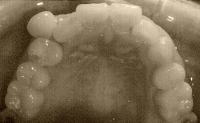

以下、画像です。

061113a.jpg 今日

061129c.jpg 今日

061129b.jpg 今日